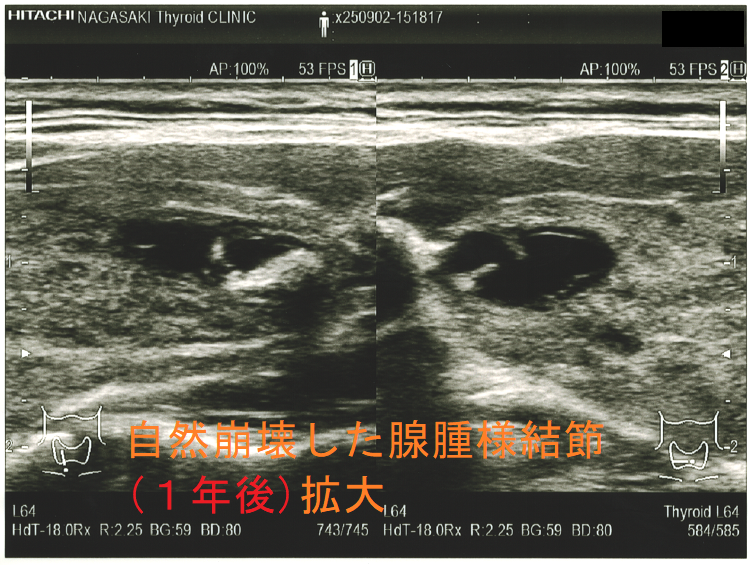

穿刺細胞診後内部融解

ケース①

ケース②